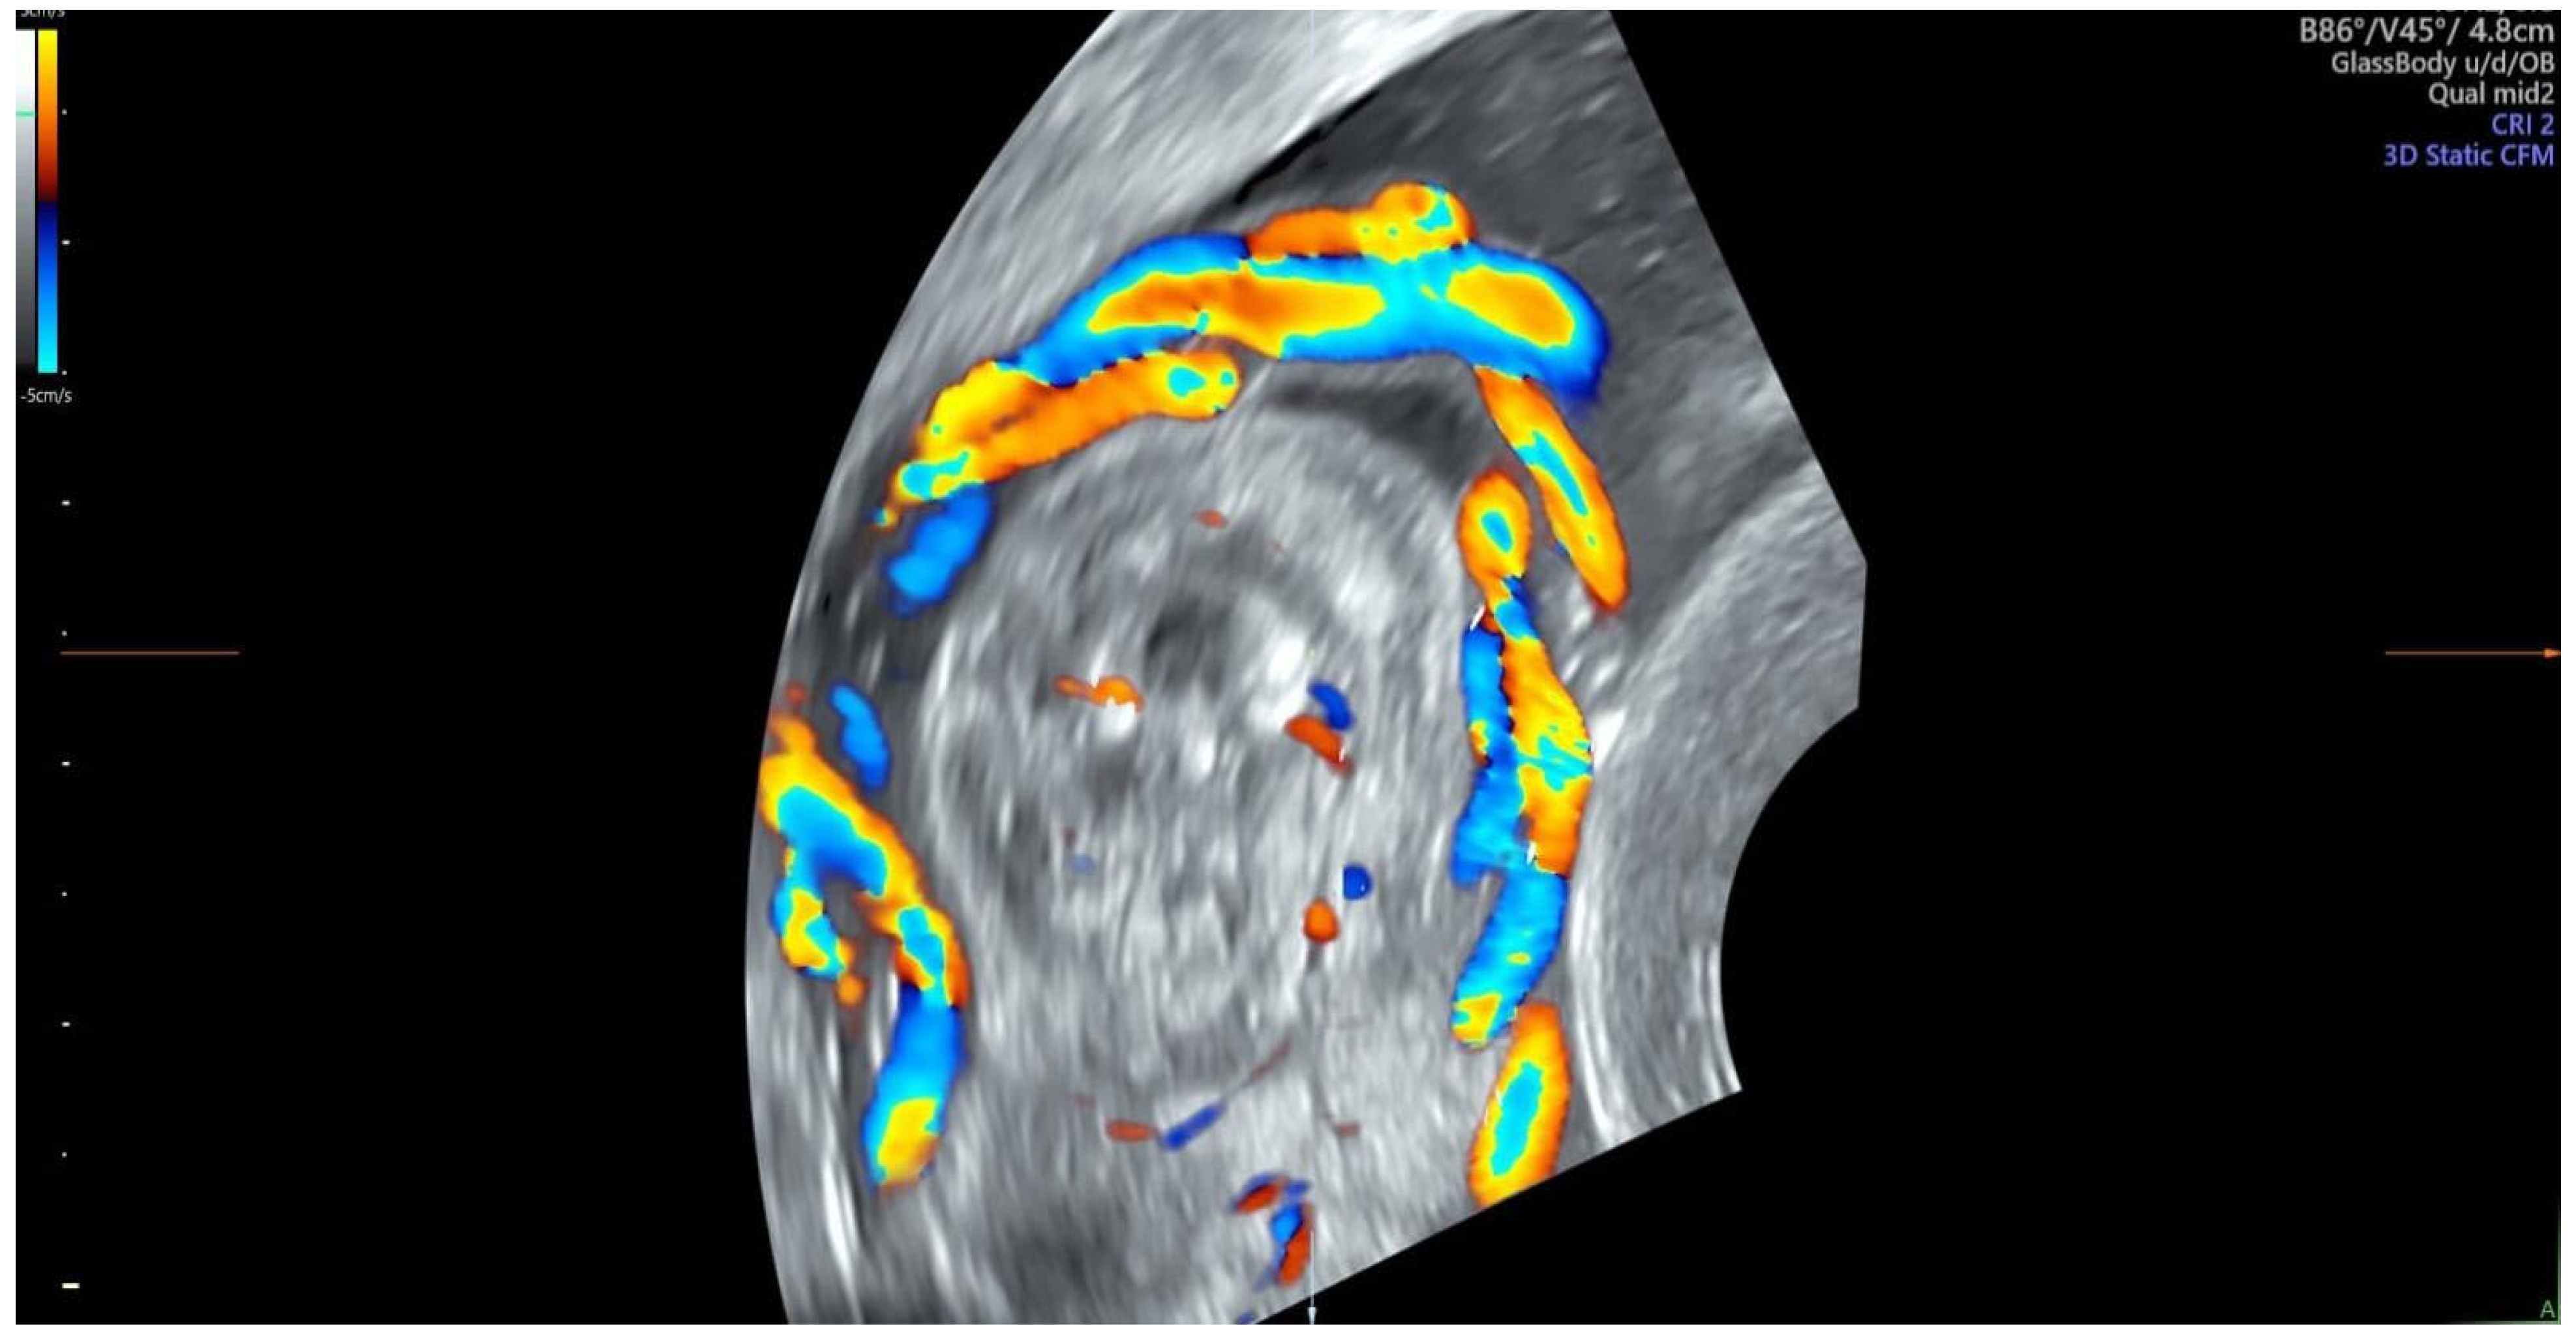

| Color Doppler |